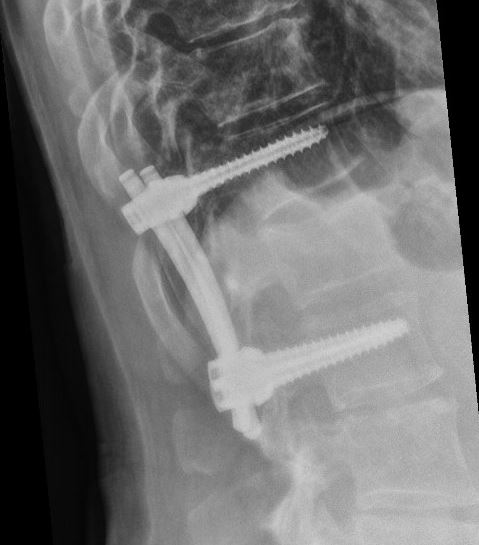

Indien u geopereerd moet worden, zijn er meerdere opties. Meestal zal er gebruik worden gemaakt van schroeven en staven aan de achterzijde van de wervelkolom om de wervels boven en onder de breuk aan elkaar vast te zetten en daarmee de breuk te stabiliseren. Soms is het noodzakelijk om aanvullend nog een stabiliserende operatie aan de voorkant te verrichten.

Zoals elke operatie, heeft ook een operatie aan de rug kans op complicaties, zoals ontstekingen van de wond, beschadiging van het ruggenmerg of zenuwen, of het alsnog inzakken van de breuk na de operatie.

Na de operatie krijgt u soms nog enkele dagen bedrust en zult u samen met de fysiotherapie het mobiliseren hervatten. Uw chirurg bepaalt of u na de operatie nog aanvullend een corset moet gebruiken.